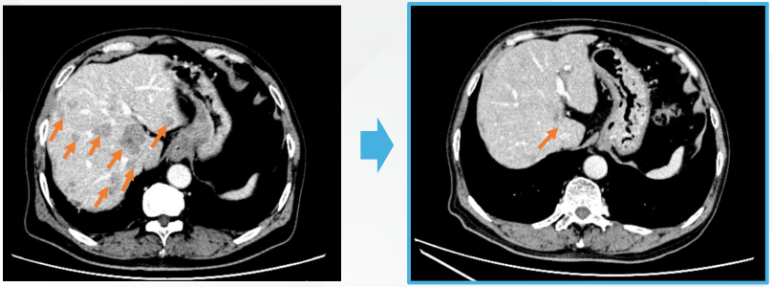

복합 면역세포치료 1사이클 후 변화

※ 복합 면역세포치료 1사이클(7회) 후 CT 결과

- 간에 보이던 대부분의 전이 병변이 소실

- 최대 직경이었던 전이 병변도 뚜렷한 축소

- 영상상 명확한 종양 신호 감소 확인

이는 단순한 “안정화” 수준이 아니라,

종양 자체가 면역 반응에 의해 제거된 전형적인 패턴에 해당합니다.